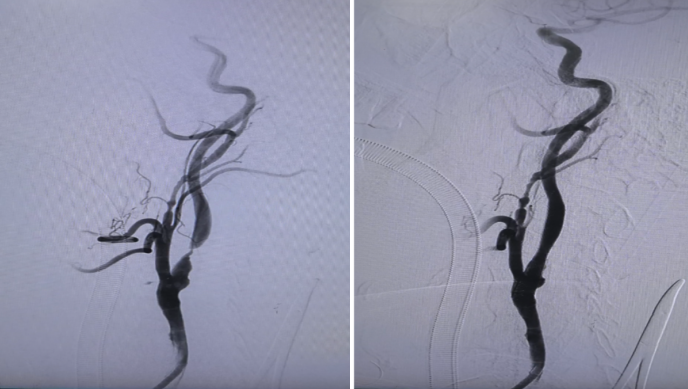

图2:术前术后对比,狭窄完全解除